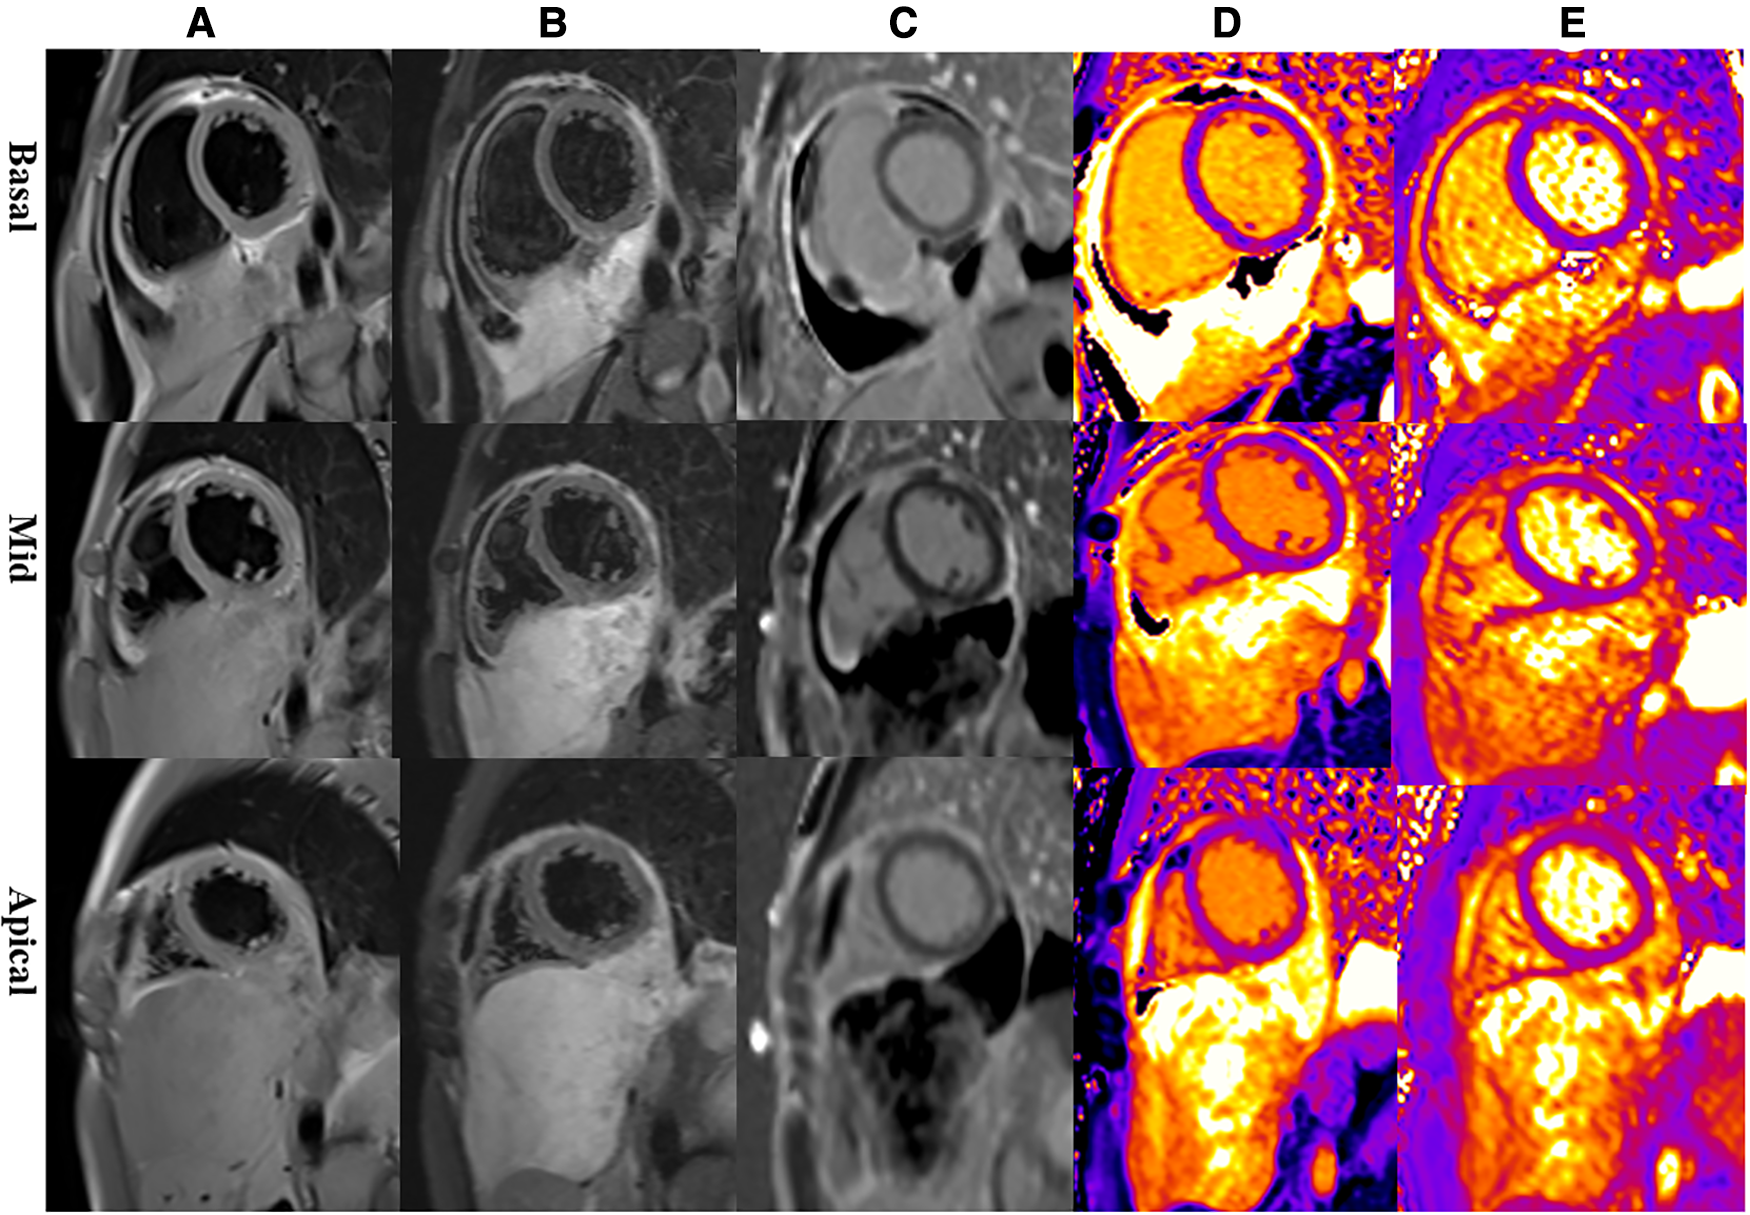

Multiparametric cardiac magnetic resonance imaging (CMR) further showed signal features suggestive for a malignant nature of the pericardial mass. Specifically, in accordance with CT, CMR showed an irregular defined mass between the pericardium and diaphragm, adjoining with enlarged lymph nodes in the right cardio-diaphragmatic angle and massive pericardial effusion (Figure 3). In cine imaging using a steady-state free-precession sequence, slight motion amplitude was observed in the large pericardial mass. However, there was no effect on the contractility of the global myocardium (Supplementary Video S1–S2). The relaxation of the inferior wall of the biventricle was slightly limited due to the compression of the adjacent myocardium by the mass (Supplementary Video S3). The analysis of cardiac function revealed preserved biventricular systolic function, with left ventricular ejection fraction at 69% and right ventricular ejection fraction at 63%. Despite the normal LV ejection fraction but elevated BNP, tissue tracking technology was used to conduct myocardial strain analysis (Supplementary Figure S2). The results indicated a decrease in the global longitudinal strain of the left ventricle (−11%; reference range: −15%–18%), while the global radial (34%; reference range: 30%–37%) and circumferential (−24%; reference range: −21%–25%) strains remained normal. These findings suggest the possibility of subtle segment contractile dysfunction due to the presence of a pericardial inflammation or a mass between the myocardium and pericardium. A conventional plain scanning sequence demonstrated a slightly hypointense appearance on T1w-imaging and a heterogeneously hyperintense appearance on T2w-imaging of the mass (Figures 3A,B, 4A,B). The presence of heterogeneously strongly elevated T1 (1,700–2,500 ms) and T2 values (120–172 ms) within the mass was also documented using T1 and T2 mapping images (Figures 4D,E). However, the native T1 (908 ms), T2 (46 ms) and extracellular volume (25%) values of left ventricular myocardium were approximately normal. Resting first-pass perfusion showed that there was a complete perfusion defect within the mass related to avascularity (Supplementary Video S4). On late gadolinium enhancement (LGE) imaging, there was no LGE core within the mass, surrounded by slightly heterogeneously high signal enhancement (Figures 3C,D, 4C). Diffusion MRI revealed that the mass was homogeneously bright on diffusion weighted imaging (DWI) and dark on apparent diffusion coefficient (ADC) (Figures 3E,F), suggestive of reduced diffusivity possibly owing to hypercellularity.

Figure 4. Representative magnetic resonance images of the basal, mid, and apical short-axis slices. (A) Dark-blood T1-weighted images show isointense mass. (B) Dark-blood T2-weighted images show strongly hyperintense mass. (C) Late gadolinium enhancement sequences reveal that there is peripheral heterogeneous uptake and a spared central core. (D) Native T1 mapping depicts evidently elevated T1 values in the mass. (E) T2 mapping depicts evidently elevated T2 values in the mass.